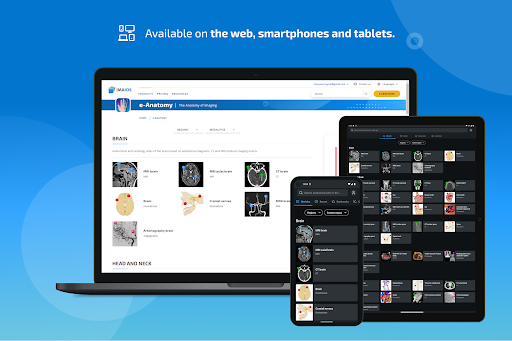

New : You can now filter the modules by region or by content type so you can find the module you are looking for much faster.